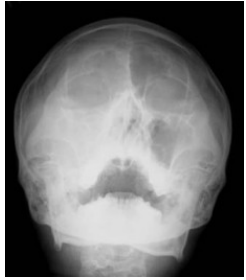

78. 此種放射線影像檢查的結果,其最可能的診斷為何?

(A) Mandibular fracture (B) Maxillary palatine cyst (C) Maxillary sinusitis (D) Fibrous dysplasia